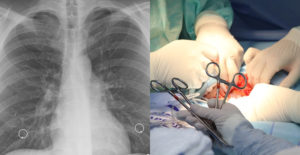

Médicos de Italia salvaron a una niña gravemente enferma mediante un autotrasplante pulmonar, la primera vez que una intervención de este tipo se practica a un paciente pediátrico, anunció el propio hospital.

La paciente era una niña de diez años de Varese (norte) que nació prematuramente de un embarazo gemelar y que padecía una cardiopatía congénita y una malformación pulmonar, en concreto una hipoplasia del circuito arterial del pulmón derecho.

La operación, que ha utilizado el propio pulmón de la niña para curar la enfermedad, ha consistido en cuatro intervenciones innovadores y de alta complejidad, y tras setenta y cinco días conectada a la Omec, la niña ha regresado a su casa, donde “podrá crecer y vivir una vida satisfactoria”.

Entre estas cuatro operaciones se llevó a cabo un autotrasplante pulmonar, el primer efectuado a esa edad y para esa enfermedad, indicó en el comunicado el doctor Andrea Moscatelli.